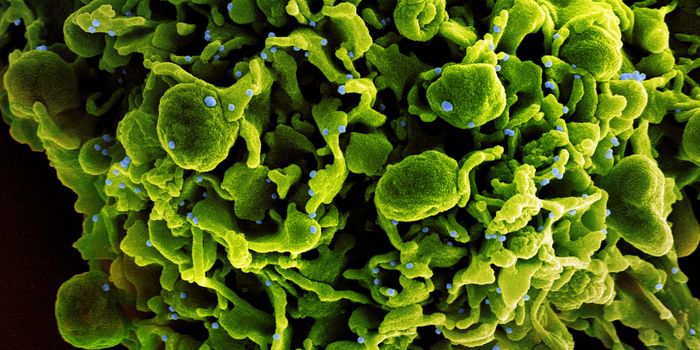

NOV 10, 2019MicrobiologyFor the first time since 2000, researchers have identified a new subtype of HIV.